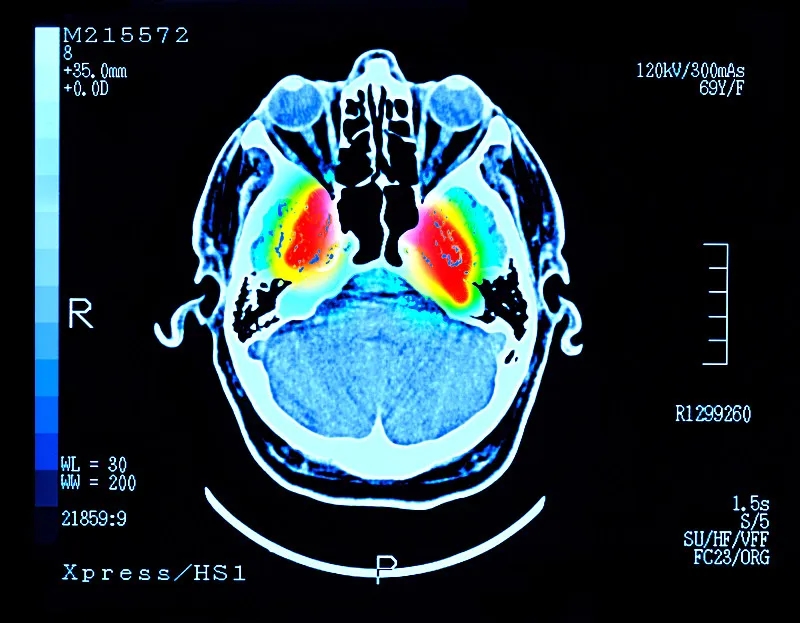

帕金森病 (PD) 是大腦中的一種疾病,它會殺死產(chǎn)生一種叫做“多巴胺”的化學(xué)物質(zhì)的神經(jīng)元。多巴胺是一種重要的化學(xué)物質(zhì),負(fù)責(zé)大腦內(nèi)神經(jīng)元之間的交流。細胞死亡主要發(fā)生在“黑質(zhì)”,這是大腦中主要的多巴胺產(chǎn)生區(qū)域。

這些治療可緩解帕金森病的癥狀,但不會減緩或逆轉(zhuǎn)大腦神經(jīng)細胞的損傷。隨著時間的推移,盡管進行了治療,但臨床特征會變得更糟。當(dāng)患者被診斷出患有帕金森癥時,他們通常已經(jīng)患病多年,并且黑質(zhì)內(nèi)的多巴胺細胞已經(jīng)丟失了一半以上。早期檢測帕金森癥的測試可能有所幫助,但科學(xué)家們正在尋找一種方法來替換受損的細胞。